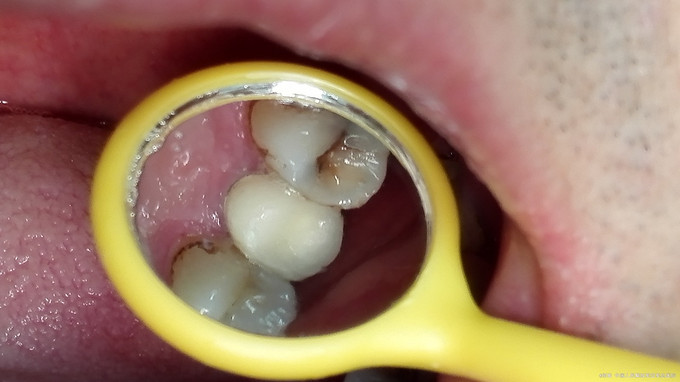

诊断:25牙体缺损 治疗计划:25玻璃纤维桩+全冠冠修复 治疗:1.取局部印模,腭根根管桩道制备,置玻璃纤维桩,堆树脂核,固化,预备牙体,取模,比色:A3, 寄送加工厂,制备临时冠,试戴,调合,磨光,粘固临时冠 2.主诉:戴牙 检查:25临时冠完好,叩痛(—),牙体无松动,牙龈未见异常 处置:戴入25全冠,调节使就位顺利,与基牙密贴,冠边缘伸张合适,邻接恢复良好,调牙合,抛光,患者满意,玻璃离子水门汀粘固,嘱须知

随着根管治疗技术的不断完善及口腔材料的不断发展,越来越多的大面积缺损的患牙得以保留,桩核技术是恢复其形态和功能的重要方法。理想的桩核材料需要具备强度高、耐腐蚀、抗疲劳、操作简便等特点。 本病例为左上第二前磨牙的近中龋坏引发牙髓炎,进而进行了根管治疗术,大量研究资料表明,根管治疗的成功依赖于两大因素,即根管治疗的质量和冠部修复的封闭性。因此,在完善的根管治疗后,冠部的修复同样对于根管治疗后牙齿的长期保留起着决定性的作用。经过认真的口腔检查,结合RCT术后牙体缺损的范围和X线牙片,患者的需求,综合分析判断患牙的保留修复方案,推荐使用玻璃纤维桩树脂核配合全冠修复。 玻璃纤维桩因其良好的生物相容性、优越的美学性能及与牙本质接近的弹性模量,能有效缓解牙本质的应力集中,且抗腐蚀、易操作、不影响医学影像成像,在临床逐渐得到推广。需要注意的是临床操作中应严格把握适应症,预备根管过程中切忌过度预备,造成根管壁薄弱,易致牙根折裂。